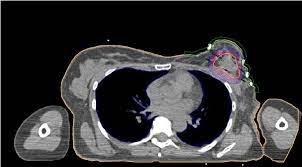

Can A Ct Scan Show Breast Cancer - Best Scans To Detect Cancer Envision Radiology : After detecting the location of the tumor, the area will be biopsied for testing in the lab.. Ct scans are inaccurate for treatment monitoring after cancer treatment, a ct scan is unable to determine whether masses leftover are cancerous: The area covered in the scanning can be determined. Bone scans, positron emission tomography (pet), and computed tomography (ct) all continue to be employed alone or in combination for the detection of breast cancers suspected to have spread. But the risk associated with these tests is worth the benefit, in most cases. A sentinel lymph node biopsy may first be performed to determine whether cancer has spread to the lymph glands under the arm.

The contrast helps to show up areas of increased vascularity and so it does help show up tumours as they have a rich blood supply. Ct scans are inaccurate for treatment monitoring after cancer treatment, a ct scan is unable to determine whether masses leftover are cancerous: Doctors often use this is for cancer staging. When a breast cancer has been diagnosed, some people have a ct scan of their chest and tummy (abdomen) to stage the breast cancer. The specialized cone beam breast ct (cbbct) scanner, developed by boone and colleagues, uses the same amount of radiation as a conventional mammogram.

Knowing the stage helps your doctor decide which treatment you need. So far, researchers at the university have. Doctors often use this is for cancer staging. Mammography is currently the preferred examination for breast cancer screening; During a ct scan, you will be exposed to a small amount of radiation. The area covered in the scanning can be determined. The test has only a limited ability to detect small tumors. The cancer's stage describes the location of cancer, if it spread and if it's changing the function of your organs. A breast pet scan is often very specific and sensitive and is approved for patients. One example is a combined pet and ct scan (known as pet/ct), available in some centers. The specialized cone beam breast ct (cbbct) scanner, developed by boone and colleagues, uses the same amount of radiation as a conventional mammogram. Ct scans can show a tumor's shape, size, and location. The contrast helps to show up areas of increased vascularity and so it does help show up tumours as they have a rich blood supply.

It's an effective imaging test for finding cancer and learning its stage. If you have a large breast cancer, your doctor may order a ct scan to assess whether or not the cancer has moved into the chest wall. The test has only a limited ability to detect small tumors. Can a ct scan pick up breast cancer. Ct scans can show a tumor's shape, size, and location.

Doctors often use ct scans to help them guide a needle to remove a small piece of tissue. Some fear that the ionizing radiation emitted from ct scans can harm dna and cause tumors. A sentinel lymph node biopsy may first be performed to determine whether cancer has spread to the lymph glands under the arm. When a breast cancer has been diagnosed, some people have a ct scan of their chest and tummy (abdomen) to stage the breast cancer. This helps determine whether or not the cancer can be removed with mastectomy. Ct scans are inaccurate for treatment monitoring after cancer treatment, a ct scan is unable to determine whether masses leftover are cancerous: This can allow for examination of neighboring organs and structures like lymph nodes to check for any signs of disease. This is an excellent way to take a needle biopsy for inflammatory breast cancer because imaging can show the best place to take the biopsy. In some cases, physicians use all three imaging techniques. Bone scans, positron emission tomography (pet), and computed tomography (ct) all continue to be employed alone or in combination for the detection of breast cancers suspected to have spread. It's an effective imaging test for finding cancer and learning its stage. How do ct scans work? The contrast helps to show up areas of increased vascularity and so it does help show up tumours as they have a rich blood supply.